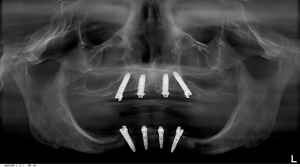

This is one of our patients. He had the posterior implants placed to avoid the sinuses on his upper jaw and his implants placed on the lower to avoid the mandibular nerve and mental foramen. This approach means NO BONE GRAFTING! Here, in the picture below, I have outlined the mesial (front) wall of the sinus on the upper, and the mandibular nerve on the lower.

Of course, we want to avoid those structures. I have illustrated how we angled the implants to eliminate the need for bone grafting. We see many patients who are told they need bone grafting in the posterior (back or rear) areas in their mouths because they don’t have enough bone back there. We treat these cases successfully nearly every day without the extensive, expensive, and time-consuming treatment periods. I’ve drawn on the X-ray below where the sinuses and the mandibular nerves are and how we avoid them. This allows us to treat our patients and finish their care, in most cases, in a matter of 3-4 months instead of 12 months or more when bone grafting is done. The All-on-4® treatment concept is a registered trademark of Nobel Biocare services AG.